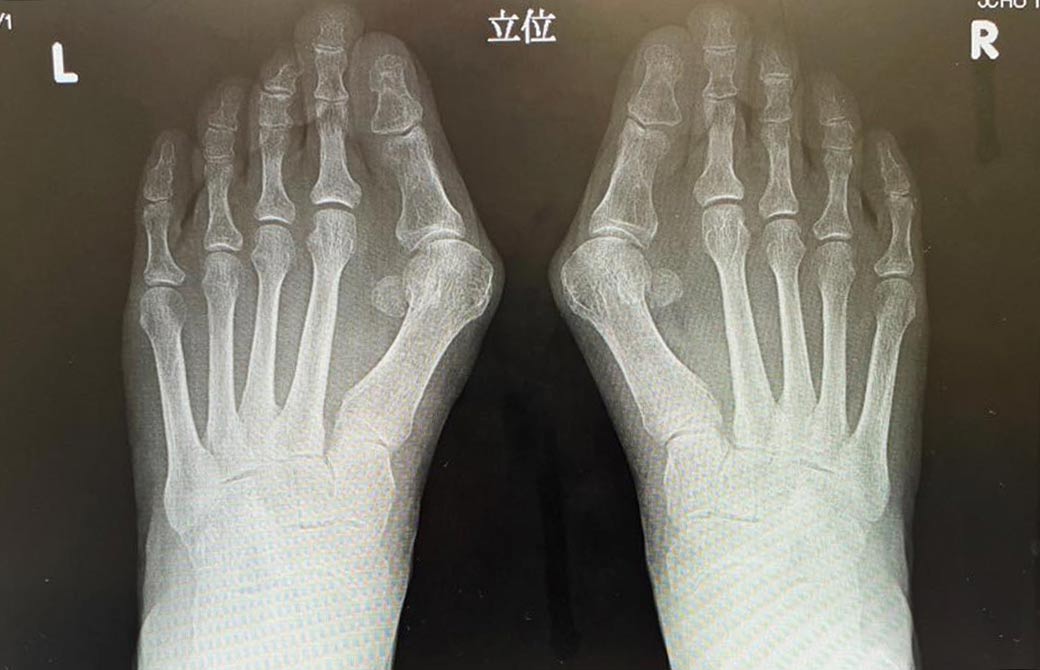

かつて、先の細い靴やハイヒールをよく履いていた、という本橋先生のお母さま。この本によると、重度の外反母趾でしたが、痛みは比較的少なく、変形だけが進んでしまっていたそう。

そこで、今回、出版社の編集長にも許可を頂き、実際にお母さまの足のお写真を掲載させて頂けることに…!

こちら、実際のお写真です。すごいですよね?たった3ヵ月でこんなに変わるんですよ!